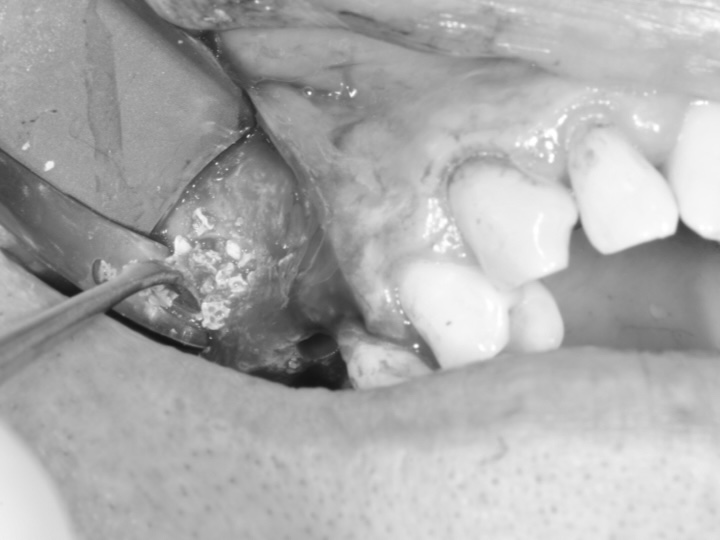

Lors d’une technique couramment utilisée, une incision est réalisée au niveau de la gencive, dans la région des prémolaires ou molaires supérieures, afin d’accéder à l’os maxillaire. Une fenêtre osseuse est ensuite créée pour permettre le soulèvement délicat de la membrane sinusienne. Un matériau de greffe osseuse est alors placé sous cette membrane afin de soutenir la formation osseuse. Le matériau de greffe peut être constitué d’os autogène, d’os d’origine donneur ou de substituts synthétiques conçus pour favoriser la régénération osseuse.

La zone opérée est ensuite refermée, et une période de cicatrisation est nécessaire avant d’envisager d’éventuelles étapes restauratrices ultérieures. Le protocole ainsi que la durée de cicatrisation dépendent de la situation clinique individuelle.